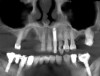

Fig 2. Preoperative view of a female patient who presented with a large defect.

Figure 2